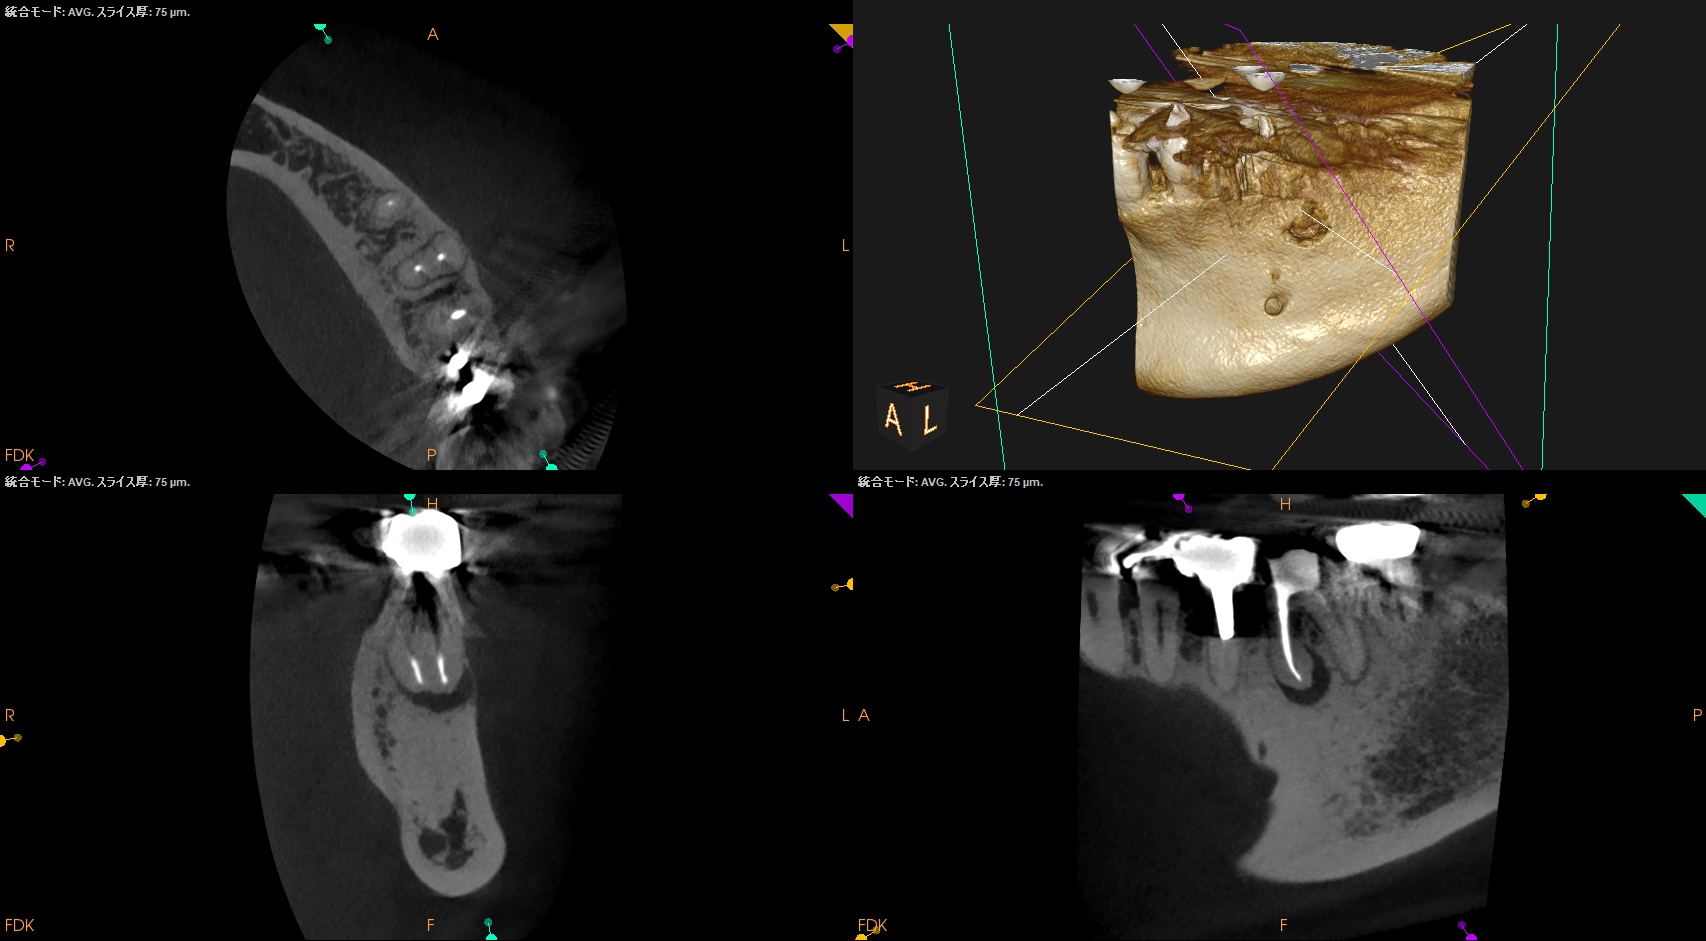

術後にPA, CBCTを撮影した。

#19 MB

#19 ML

#19 D

問題はないと思われる。